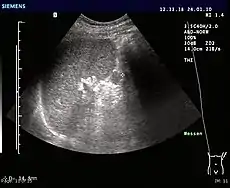

Ultrasonography of an accessory spleen.

An accessory spleen is a small nodule of splenic tissue found apart from the main body of the spleen. Accessory spleens are found in approximately 10 percent of the population[1] and are typically around 1 centimetre in diameter. They may resemble a lymph node or a small spleen. They form either by the result of developmental anomalies or trauma.[2] They are medically significant in that they may result in interpretation errors in diagnostic imaging[2] or continued symptoms after therapeutic splenectomy.[1] Polysplenia is the presence of multiple accessory spleens rather than one normal spleen.

If splenectomy is performed for conditions in which blood cells are sequestered in the spleen, failure to remove accessory spleens may result in the failure of the condition to resolve.[1] During medical imaging, accessory spleens may be confused for enlarged lymph nodes or neoplastic growth in the tail of the pancreas,[5] gastrointestinal tract, adrenal glands or gonads.[2]